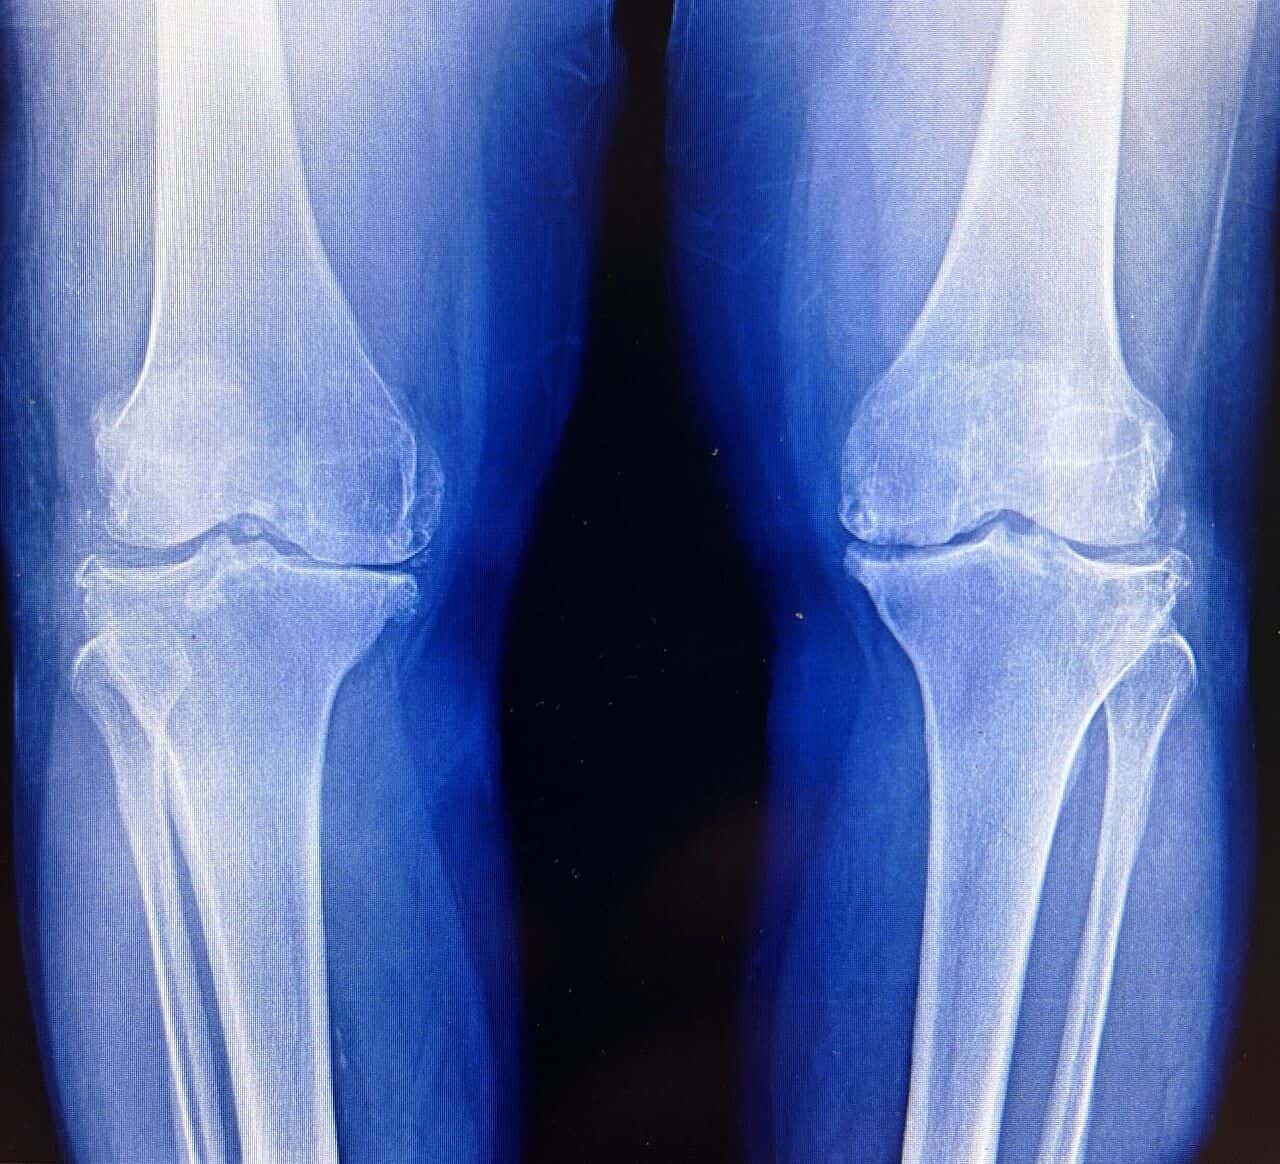

Cartilage is the body’s most stubborn tissue. Once it wears away, it’s usually gone for good. This biological dead-end is the engine behind osteoarthritis, a grueling condition that stiffens joints,…